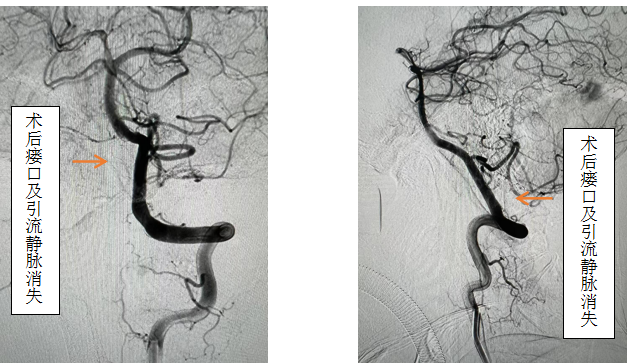

先进的复合手术室,首先采用第一方案“高压锅”技术使胶完全封堵瘘口,若不能到位或完全封堵,则采用第二方案,转为开颅阻断瘘口。手术当日,由黄卫东主任医师和李帅主治医师操作,第一根栓塞微导管顺利到达瘘口,第二根微导管接近栓塞微导管后使用弹簧圈顺利形成高压锅塞子,经第一根微导管注入栓塞胶,射线透视下见栓塞胶按预期流向瘘口,栓塞满意后造影示瘘口及引流静脉均未见显影,手术成功。术后患者恢复良好,第二天即下床活动,下肢活动明显恢复,5天后步行出院。